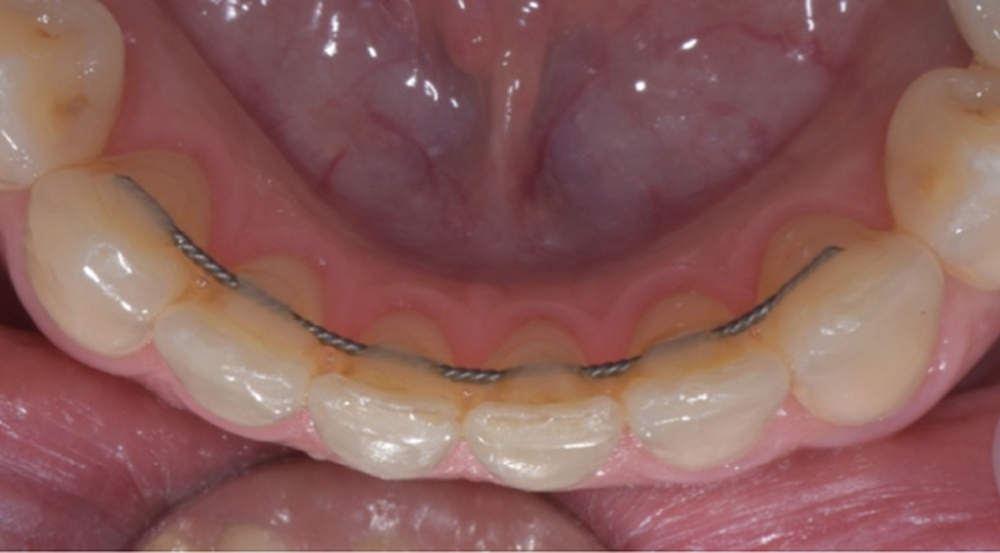

Bien que 23 % des patients reconsultent dans les dix années qui suivent la dépose de leur appareil [5], la contention est longtemps restée le parent pauvre des nouvelles technologies. Ceci est en train de changer et le Dr Serge Dahan nous éclairera sur l’apport des outils numériques, dans la réalisation des contentions de nouvelle génération. Ces dernières peuvent être fixes ou amovibles.

Dans le premier cas, il s’agit de plaques de nickel-titane usinées (fig. 10a-b) ou de fils de contention, pliés par un robot. Dans le deuxième cas, il s’agit de gouttières thermoformées sur des modèles (fig. 11), modifiés ou non, voire bientôt des gouttières imprimées directement.